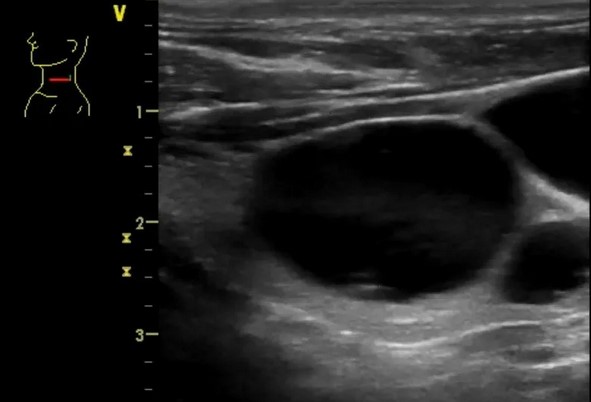

УЗИ диагностика кольцевидной поджелудочной железы: что важно знать